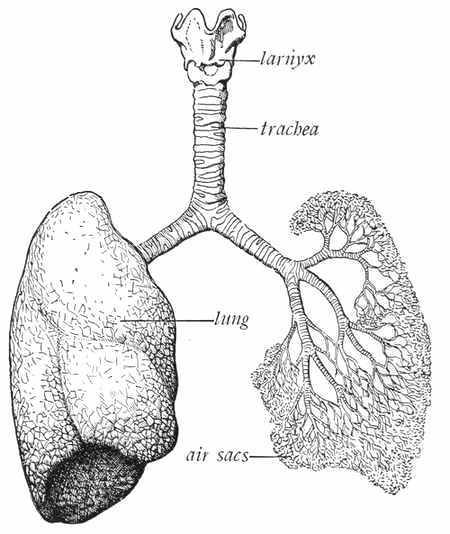

We have learned how the cells of the body are killed by starvation. Now let us learn how they are choked to death, or killed by lack of air.

The cells of the body need oxygen, and the only way we can give it to them is by means of air. Every time we take air into our lungs we are giving oxygen to the red corpuscles or cells in the blood, which distribute it to the other cells in the body. The air that goes into our lungs, if it is fresh and pure, contains a great deal of oxygen and a very little of another gas called carbon dioxid. The air that comes out of the lungs contains a very little oxygen and a great deal of carbon dioxid. The blood not only takes the oxygen out of the air, but gives carbon dioxid to the air. This carbon dioxid is very poisonous, and would kill the cells if it remained in the blood; hence we should never breathe the same air twice. There is no lack of fresh air in the world, and no excuse for anyone's ever breathing air that is not pure.

If you close all the windows and doors in the schoolroom and shut up the ventilators, you will soon find that you are not able to pay close attention to your studies, and in a little while you will begin to feel drowsy. This is because you have used up so much of the oxygen in the air that there is no longer enough to supply the demands of the little cells, and because, in addition, you are taking into your bodies the poisonous carbon dioxid that has been breathed out into the room. It takes a great deal of fresh air to supply the body with oxygen—about 1,250 cubic feet of air each hour. With thirty or forty children in a room, it does[46] not take long to use up all the oxygen. So there should be a constant supply of fresh air coming into the room.

It is not only in the schoolroom that you need oxygen. When you are out-of-doors you get an abundance of fresh air, but from a great many houses every bit of fresh air is shut out. It is always possible to let an abundance of fresh air into any house without causing a draft. A piece of board can be made to fit into a window frame so that when the window is raised, the air will be directed upward and will not cause a draft. Hot-air furnaces are made with cold-air pipes. The fresh air from outdoors comes through these cold-air pipes and, after being heated, is driven into the rooms of the house. Some people think they will save coal by closing these drafts. Not only do they not save coal (for the furnace does not give as much heat when this draft is closed), but they kill their body cells by refusing to give them oxygen. The cold-air pipe in a hot-air furnace should always be kept wide open.

In houses heated with steam or hot water, either the windows must be kept open, or some other way must be provided for admitting fresh air and taking out foul air. These arrangements constitute a system of ventilation. Houses heated with stoves must also be provided with some means[47] of ventilation. The stove, by its draft, takes out a little of the foul air, but it will not take out more air than one person poisons.

The cells in the skin of the nose secrete a watery fluid, and this fluid serves to moisten the air as it passes through the nose. Dry air irritates the mucous membrane which lines the nose, throat, and lungs, and it is very important that the air be moistened before it reaches the throat. Air is also warmed as it passes through the nose. Cold air is irritating to the throat and lungs. The small hairs in the nose catch the dust and dirt in the air and prevent it from going into the lungs.

The nose was made to breathe through, and all the air[49] that goes into your lungs should pass through your nose, in order that it may be moistened, warmed, and cleansed.